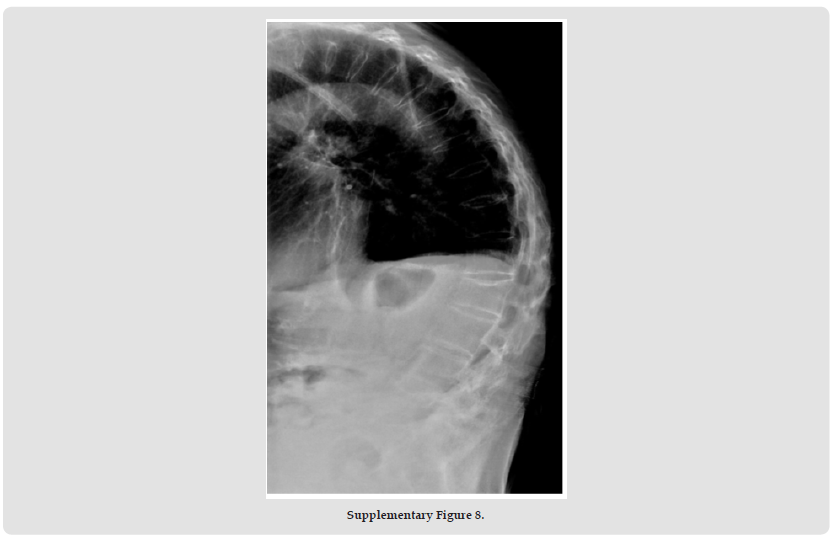

Psoriatic arthritis (PsA), a systemic autoimmune disease, manifests with remarkable clinical heterogeneity [1]. While axial involvement and peripheral joint destruction are well documented, the coexistence of severe spinal kyphosis and Mutilans-type arthropathy remains exceptionally rare. We present a diagnostically challenging case with concurrent progressive spinal deformity and osteolytic features of Mutilans [2]. This case report describes the complex clinical presentation of a rare psoriatic arthritis (PsA) patient with severe kyphosis and mutilating arthritis. A 69-year-old woman with a 50- year history of psoriasis developed worsening skin symptoms and joint pain in 2019. She was treated with cyclosporine, ezicizumab and secukinumab, which resulted in partial relief of skin symptoms but progressive joint destruction. Over the past two years, he had developed a complex sagittal and coronal spinal deformity (thoracolumbar kyphosis with scoliosis), accompanied by characteristic “telescopic” phalangolysis and ulnar deviation of the right hand. His serum markers (RF, anti-CCP, etc.) were normal. Imaging showed the coexistence of heterotopic ossification and osteolysis, consistent with the diagnosis of residual PsA combined with spinal PsA. The clinical significance of this case is that it highlights three key issues. Firstly, rapidly progressive spinal lesions can occur in the absence of a typical serological marker (negative HLA-B27); secondly, biological agents can cause separation of skin and joint effects.

Third, mechanical stress may accelerate the progression of spinal deformity in susceptible individuals. This suggests that dynamic monitoring of the spine in PsA patients should be intensified, especially in patients with long-term good skin control but new axial symptoms, and the evaluation strategy should be adjusted. Future research needs to further explore the mechanical-inflammatory interaction mechanism and establish precise treatment pathways for different clinical phenotypes. This case provides an important clinical demonstration to recognise the heterogeneity of PsA and the complexity of treatment (Supplementary Figures 1-11).